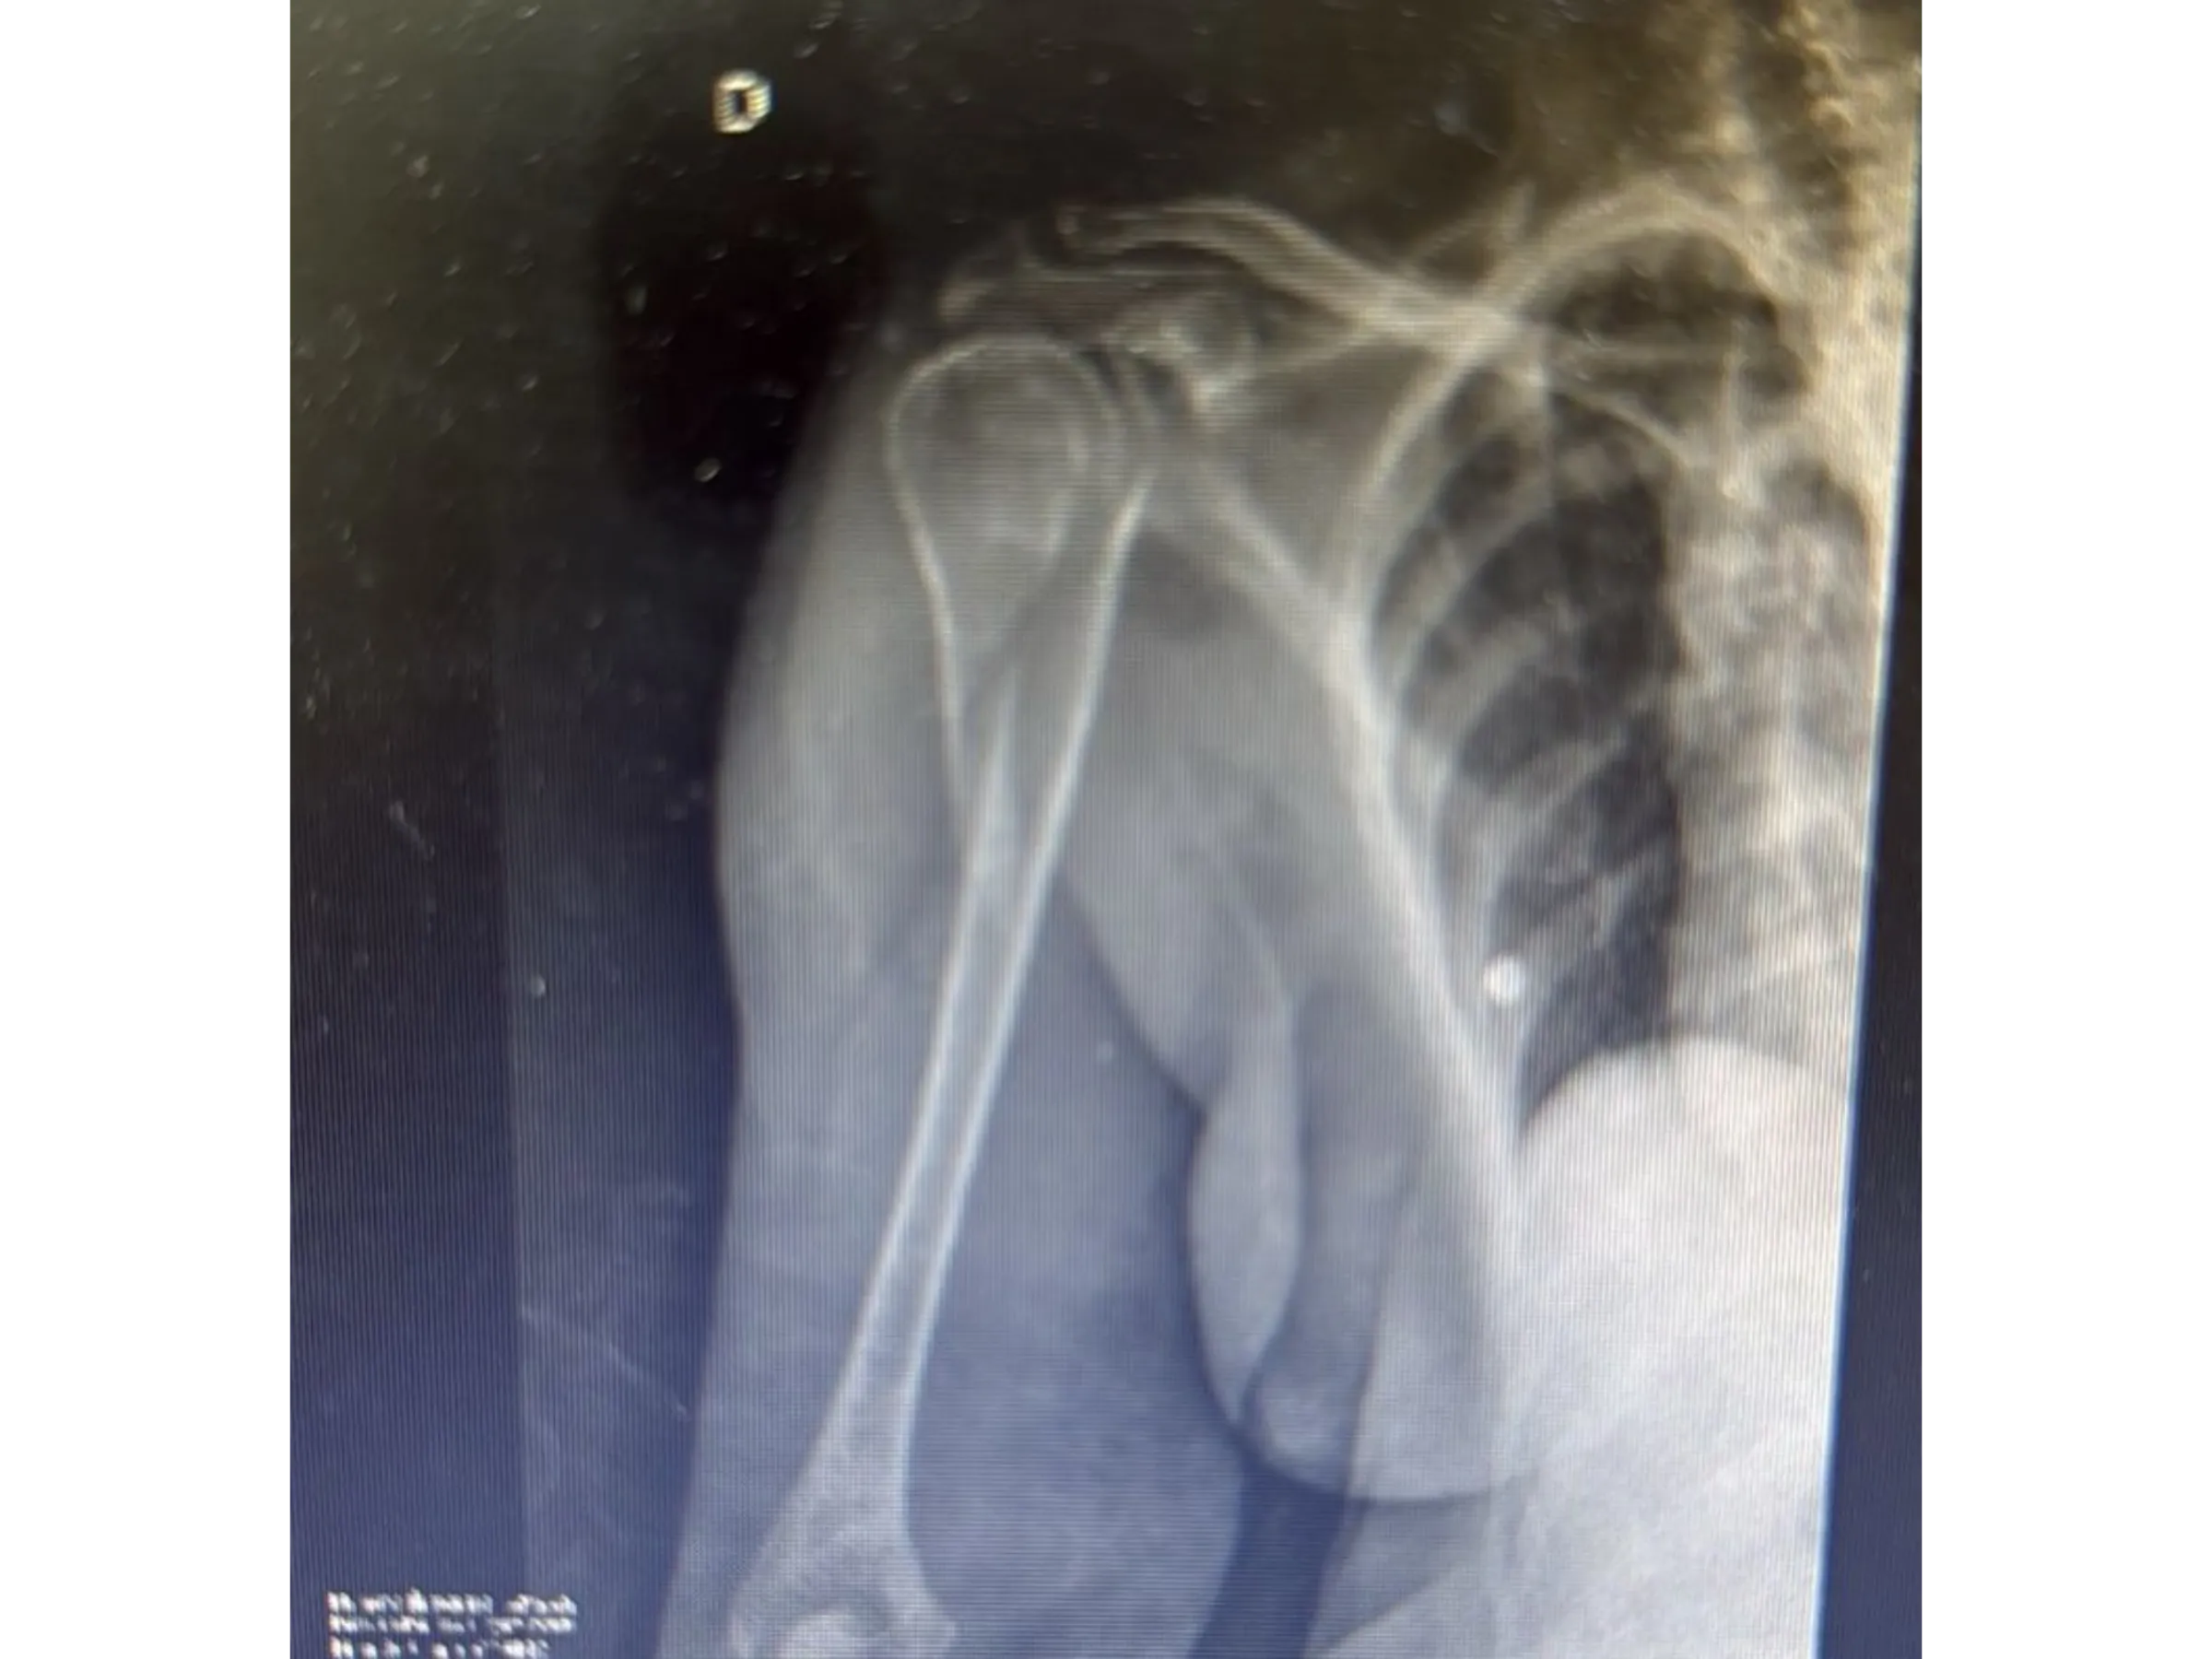

Proximal humerus fractures in elderly patients require effective stabilization with minimal tissue damage. This training presents a fluoroscopy-guided surgical approach using a long intramedullary nail that preserves the rotator cuff and ensures secure fixation. The technique is demonstrated step-by-step from a surgical perspective, focusing on anatomical and biomechanical precision.

- Precise Radiographic Marking: Use of Kirschner wires and dermography for sagittal alignment.

- Rigorous Fluoroscopic Control: Anteroposterior and lateral images to ensure parallelism and precision of the implants.